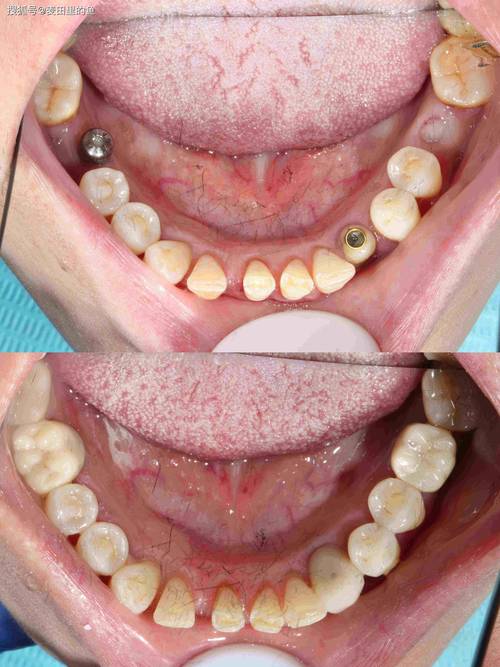

珠海植牙流程通常分为术前检查、方案设计、手术植入、戴牙冠及术后维护五个阶段,周期根据患者骨条件和个人需求差异,一般为3-6个月。

- 手术植入:在局部麻醉下,通过微创手术将种植体植入牙槽骨,手术时间约30分钟-2小时(单颗/多颗差异),术后无需住院,当天可正常饮食(避免患侧咀嚼)。

- 戴牙冠:种植体植入后需3-6个月骨结合期,待种植体与牙槽骨稳固后,通过基台连接牙冠(全瓷冠、烤瓷冠等),恢复牙齿形态与功能。